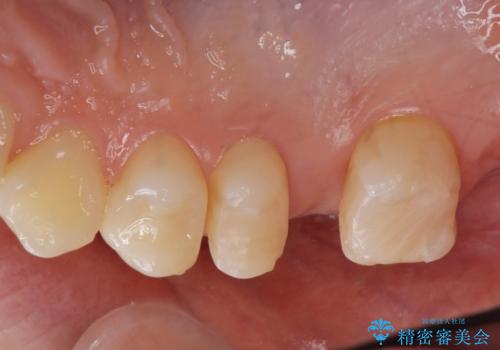

- ジルコニアクラウンブリッジ(スタンダード)・仮歯・部分矯正(upライト) 50.6万円費用は治療当時の料金となります

適合の良いブリッジが入りました。

歯の傾きを改善することにより食べ物が詰まりにくくなりました。

白い被せ物が入り、満足して頂けました。